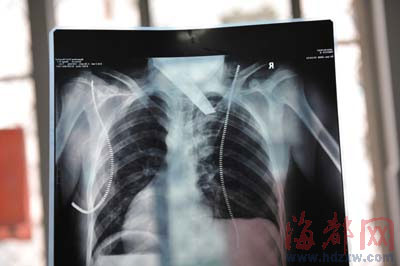

前晚,在第一医院急救室,经过4个多小时的抢救,医生将匕首从小勇身上取出,发现这把匕首的刀尖扎断了1厘米。由于小勇肺部被刺中,昨天上午,医生再次进行了3个多小时的手术,切除了受伤的部分肺,直到下午,小勇才挺过来。“挺了一夜,现在总算醒了过来。”杨女士一夜没睡,守在手术室外7个多小时,生怕儿子再醒不过来。不过,由于伤势严重,小勇目前戴着氧气呼吸,仍未脱险。